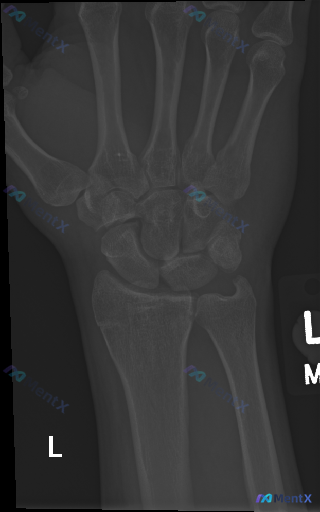

左手腕关节正位X光片未见明确异常,这种情况怎么考虑更稳妥?

整理到一份左手腕关节正位X光片的客观读片资料,大家可以一起看看这种情况怎么考虑更稳妥。

- 骨骼完整性与序列:近排与远排腕骨排列关系基本正常,无明显脱位/半脱位,舟月间隙无异常增宽;桡骨远端、尺骨远端及各腕骨皮质线连续,未见明确骨折透亮线(重点观察了舟骨腰部、桡尺骨茎突);骨小梁结构清晰,无明显压缩或中断。

- 关节间隙与对合:桡腕关节、中腕关节、下尺桡关节间隙宽度尚均匀,对合良好,无明显阶梯感或脱位。

- 骨密度与骨质:整体骨密度无明显异常减低或增高,未见明确溶骨性破坏、膨胀性改变或成骨性硬化灶;关节边缘无明显骨赘或关节面硬化,暂未见明显退行性骨关节炎征象。

- 软组织与异物:腕关节周围软组织轮廓大致平滑,未见明显肿胀或异常高密度影;无明确金属异物或病理性钙化。

- 发育与变异:骨骼发育成熟,骨骺线均已闭合;未见明显副骨或融合畸形等先天变异。

单看这份正位片的客观结果,没有发现明确的骨折、脱位、骨质破坏或关节病变。